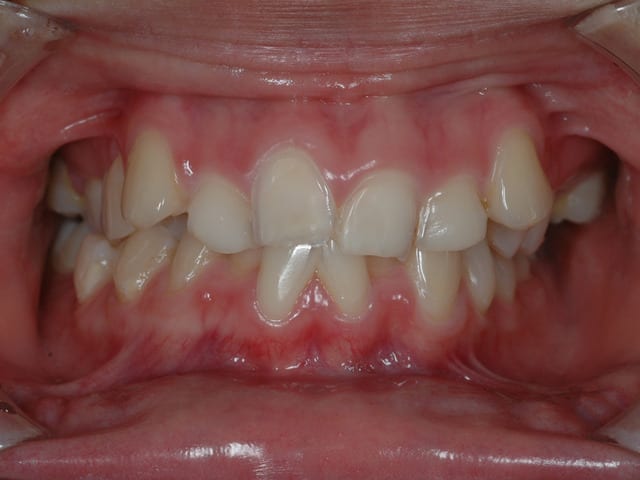

Ayant apprit de mes erreurs, j'ai compris qu'il n'était pas conseillé de poser une devinette en rapport avec les pathologies osseuses si je ne voulais pas que canin me la pourrisse si tôt connecté. Soupçonnant que le résultat serais le même avec une pathologie gingivale (et n'ayant rien d'approprié de toute façon) je me tourne vers les tissues dentaire

Patiente de seize ans, vivant dans une grande métropole Thailandaise.

A votre avis quel est l'étiologie de l'usure de l'email sur les incisives central supérieure.

Ps : impossible car quand j'ai appris l'étiologie je me suis demandé ce que la patiente avait fumer pour me sortir une ânerie pareille. En fait l’âne c'était mois et l'étiologie donné par la patiente était la bonne.

Si j'ai mis une vue vestibulaire et occlusal il y a une raison